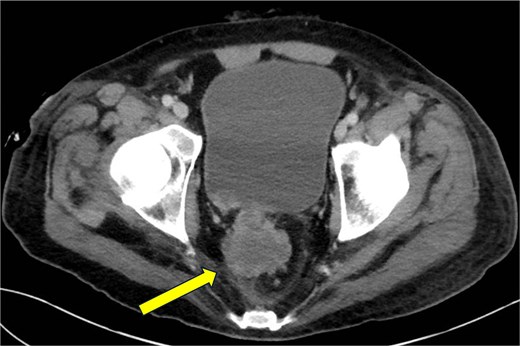

Three weeks later, the patient presented to a rural ED with fevers documented to 103.5°F (39.7°C), intractable low back pain and in severe sepsis. Hemodynamics stabilized following fluid resuscitation. He received vancomycin and meropenem prior to transfer to our facility. There was exquisite tenderness overlying the midline lumbar spine and uninfected, healing granulation tissue overlying previous perianal fistulae. His white blood cell count (WBC) was 26.21, CRP was 42.6 mg/dl (0–0.8 mg/dl) and lactate was 5.2 mmol/l (0.5–2.0 mmol/l) and glucose 99. Blood cultures were negative. CT imaging identified extensive intraosseous gas involving the right pubic ramus, sacrum, bilateral ilia, T6 and T7 vertebral bodies, L1 and L2 vertebral bodies, left proximal femur, sternum, and multiple ribs bilaterally. Soft tissue gas was additionally identified within the right obturator internus and right adductor longus (Figs 2–5). A diagnosis of EOM was made. Daptomycin, cefepime, and metronidazole were started per infectious disease.

CT abdomen and pelvis—axial plane. Intraosseous gas is seen in the left femur at roughly the level of the lesser trochanter (yellow arrow, right). A previously drained perianal abscess (blue arrow, left).